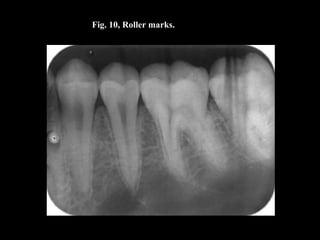

Fig. 10, Roller marks.